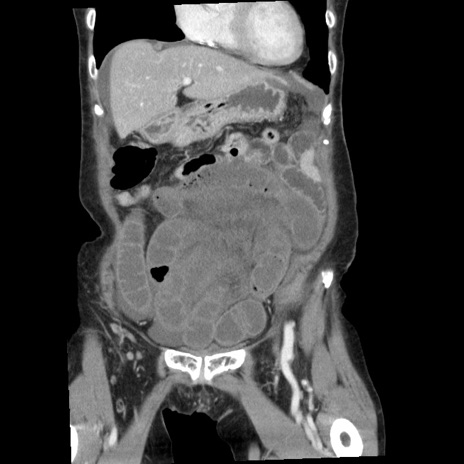

症例1(冠状断像)

【症例】80歳代女性

【主訴】腹痛

【現病歴】8時間前から腹痛あり来院。

【既往歴】糖尿病、脂質異常症、子宮体癌にて子宮全摘術

【身体所見】意識清明・会話良好だが腹痛で苦悶様、全腹部にわたって反跳痛と圧痛あり

【データ】WBC 13600、CRP 0.14、LDH 224、CK 90